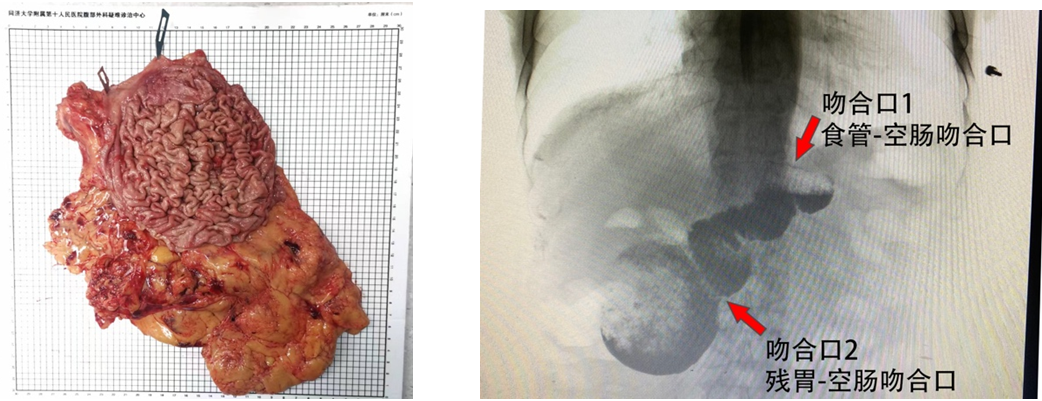

(术后标本图+术后造影图)

患者手术顺利,术后未出现吻合口出血、吻合口瘘、反流性食管炎等常见并发症。随访至今近1年期间,各项肿瘤指标正常,腹部CT等亦未见肿瘤复发转移证据。